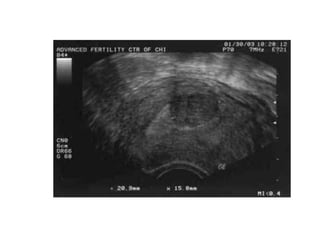

PATHOLOGY

• May reach 15 cm in size or larger